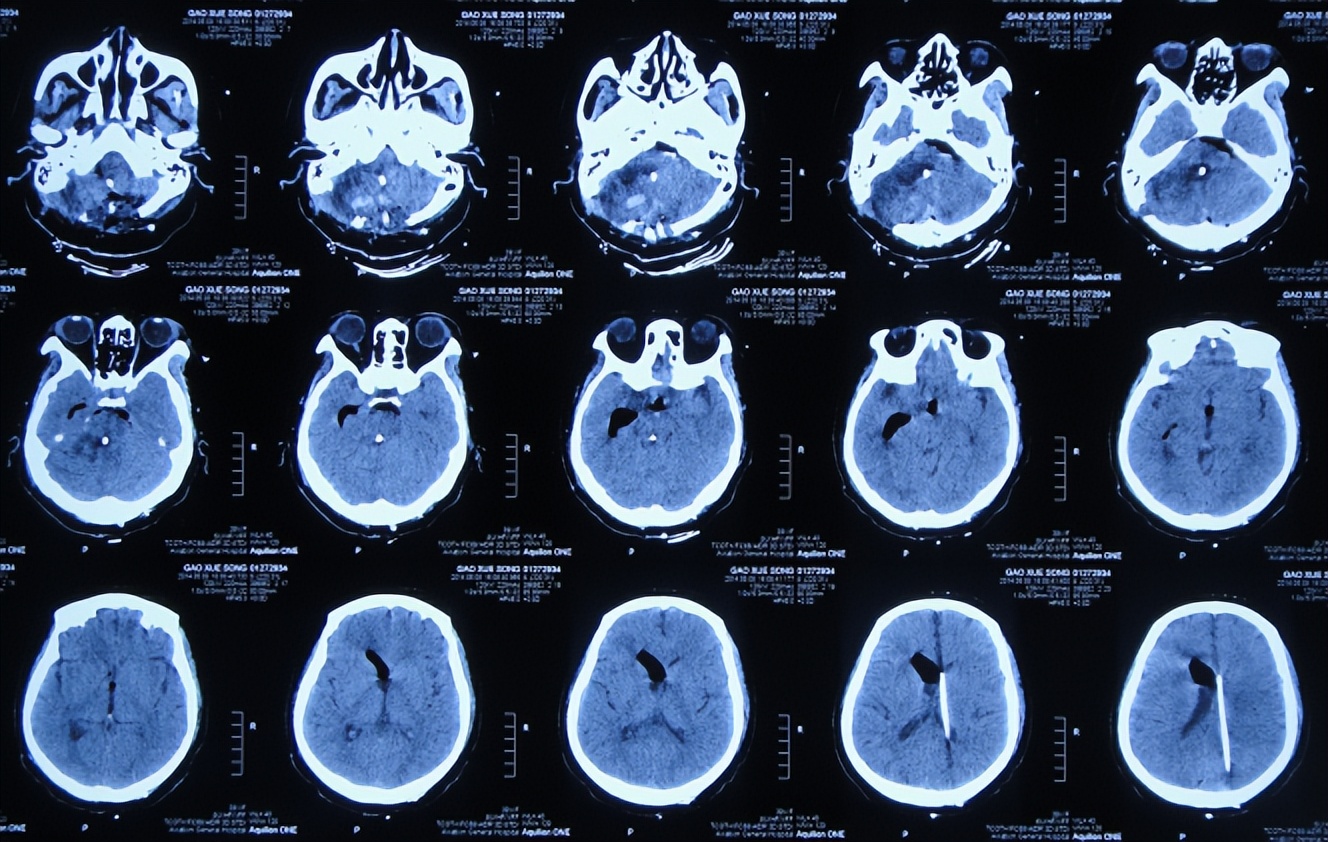

患者高老师是一名高中历史教师,右耳听力减退已10余年未给予特殊治疗,但2013年11月因出现病情严重的头疼头晕症状,到当地的山西省静乐县某医院,查头颅CT(图-1)后颅内肿瘤占位,需要手术。

图-1:2013年11月6日头颅CT